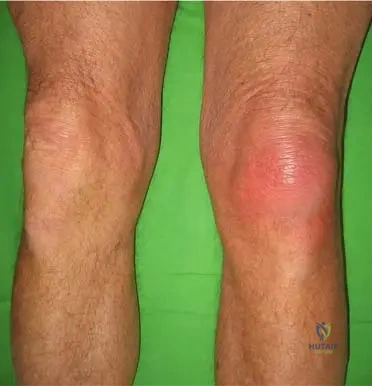

A 58-year-old male presents to the emergency department with sudden, excruciating pain and swelling in his left knee. Examination reveals a hot, erythematous, and exquisitely tender knee joint.

Correct Answer: D

Rationale: While the first metatarsophalangeal joint (podagra) is the most common site for acute gout, the clinical context for Fig. 7.4 explicitly shows an "Acute gout spasm of the left knee," indicating that the knee is another frequently affected large joint. The ankle is also a common site, but the image specifically depicts the knee.